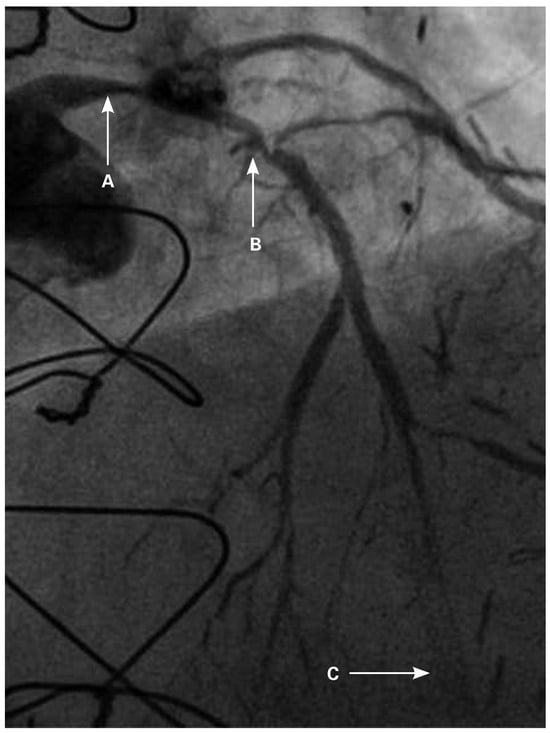

Veno-arterial extracorporeal membrane oxygenation (ECMO) is utilised as a short-term mechanical circulatory assist device for treatment of refractory acute cardiogenic shock. After a period of support, called “bridge to decision”, the options for ens...